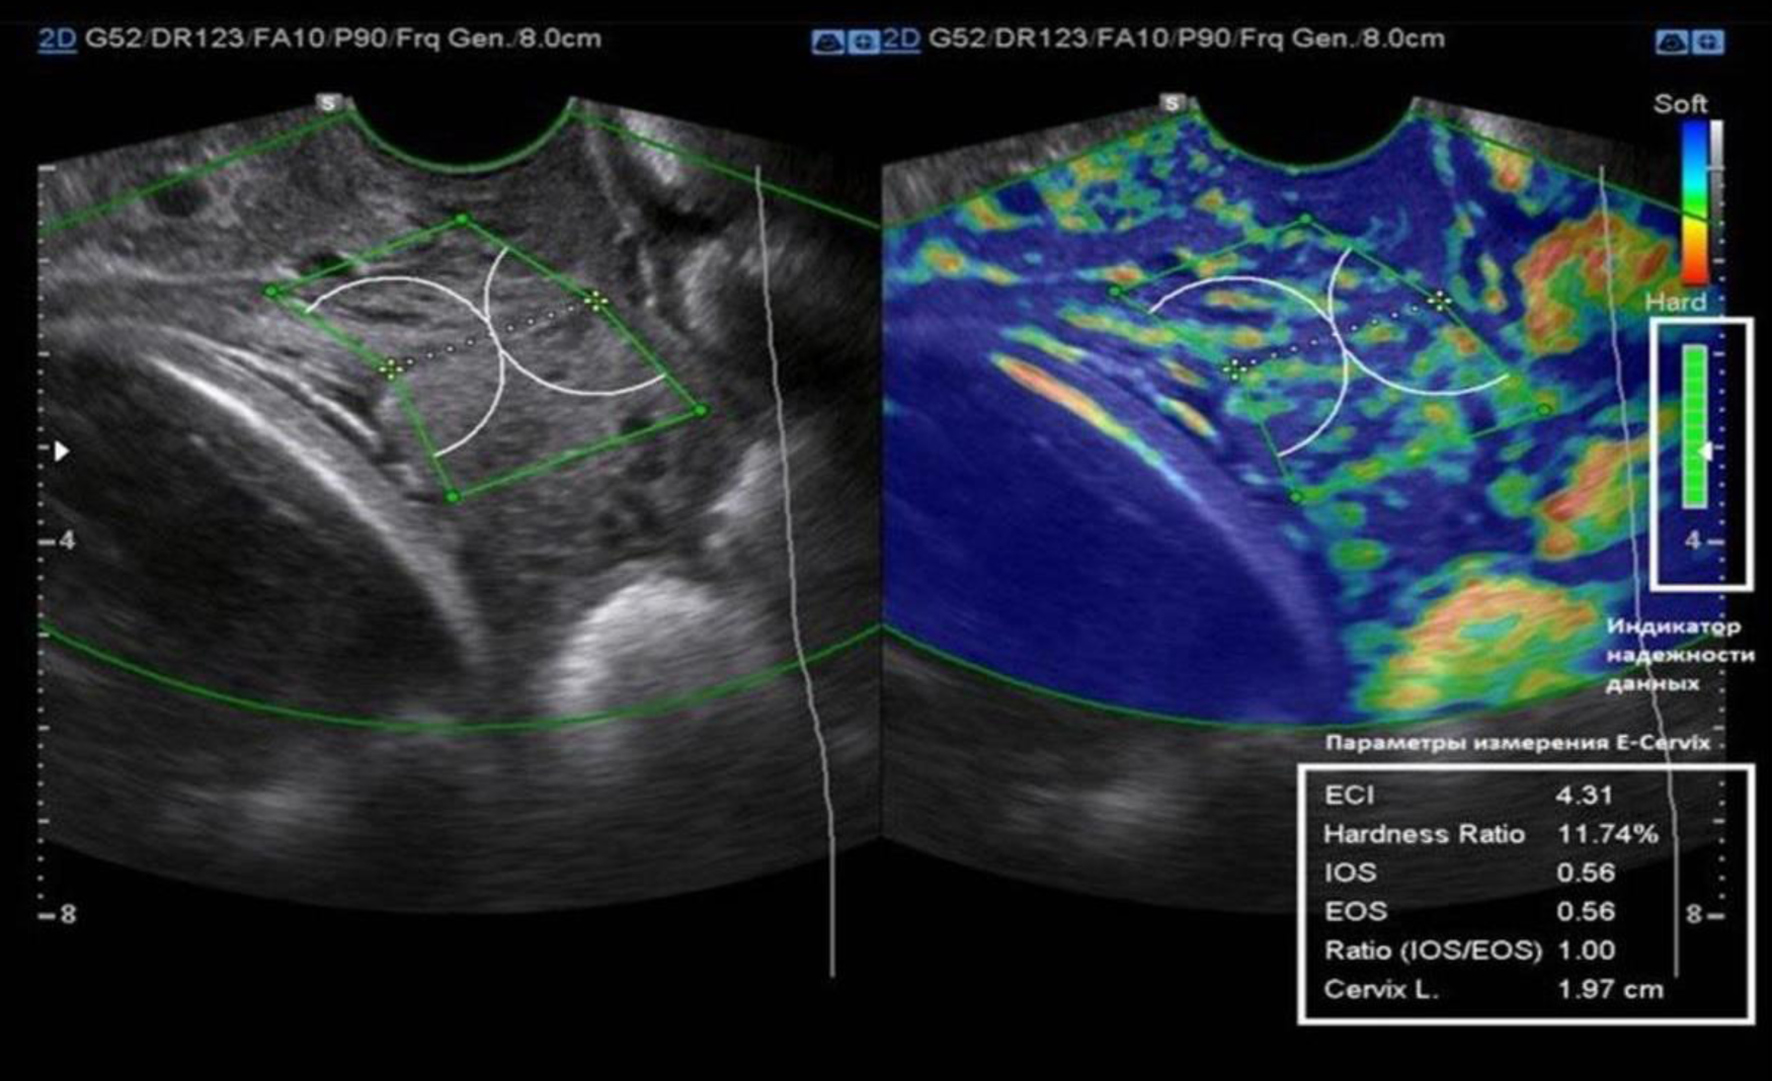

Figure 2 demonstrates the E-Cervix screen, assessing the stiffness of the cervix. The color map displays areas with different levels of stiffness, and the indicators of the ECI and the ratio of the average level of deformation in the area of the IOS and EOS (ratio IOS/EOS) are presented on the right side of the screen. Green blocks indicate reliable data acquisition.

Figure 2. E-Cervix screen for cervical stiffness assessment.